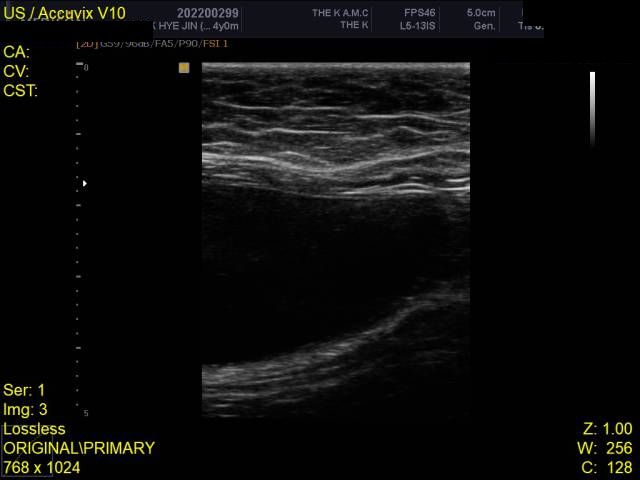

HCM의 진단의 golden standard 는 심장초음파 검사입니다. 하지만 첨부된 자료에는 심장 초음파 검사 결과가 없고

흉부 방사선 검사 또한 외측상이 결여되어 있어 자료로 판단할 수 없습니다.

주치의에게 요청하여 심장 초음파 검사를 진행해 보시기 바랍니다.